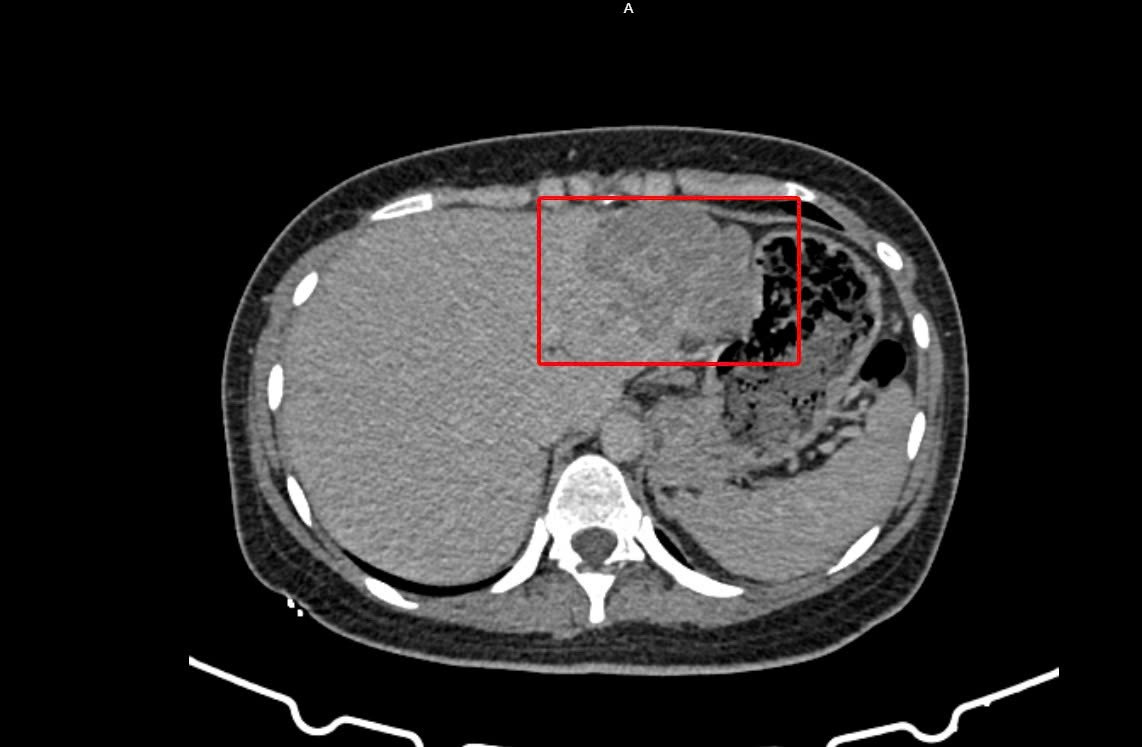

Cô gái trẻ bị ung thư gan ‘đánh úp’ sau 2 tháng đau âm ỉ- Ảnh 1.

Vùng gan bị tổn thương trên hình ảnh kiểm tra được các bác sĩ ghi nhận

Kết quả cho thấy bệnh nhân bị viêm gan siêu vi B, đồng thời chỉ số AFP (dấu ấn quan trọng trong tầm soát ung thư gan) tăng cao. Hình ảnh CT-Scan bụng có cản quang cũng ghi nhận tổn thương phù hợp với u gan, ung thư biểu mô tế bào gan.